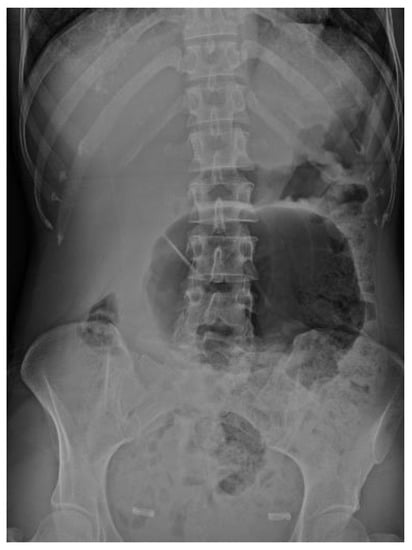

4.4.1. Conventional Radiography

- CT scan confirms diagnosis in >90%

- Typical Radiological Signs are described

- Representative X-ray and CT images presented

| Abdominal radiograph | 11 (68.75%) | Five patients had CT as the only imaging. |

| Non-specific bowel loops/SBO | 5 (46%) | |

| Classical single loop of large bowel | 6 (54%) | |